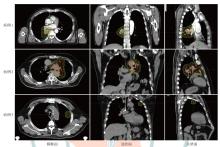

目的 探讨质子调强放疗(IMPT)和固定野调强放疗(IMRT)应用于肺癌的剂量学特点。 方法 选取2024年1月至2024年5月山东省肿瘤防治研究院(山东省肿瘤医院)收治的3例肺癌(中央偏下型、中央型和周围型)患者为研究对象,根据临床靶区解剖结构位置和危及器官限值的要求,分别设计IMPT和IMRT两种放疗计划。评估3例患者两种放疗计划的靶区适形指数(CI)、均匀性指数(HI)、梯度指数(GI)以及危及器官的剂量学指标,通过评估体内10%、30%和50%处方剂量区域的体积比较患者体内额外的剂量沉积。 结果 3例肺癌患者IMPT计划的CI值(分别为0.61、0.57和0.34)、HI值(分别为0.07、0.06和0.06)、GI值(分别为2.84、2.47和4.56)均小于IMRT计划(CI分别为0.80、0.60和0.79;HI值分别为0.09、0.15和0.09;GI值分别为4.91、3.09和4.99)。与IMRT计划比较,IMPT计划患侧肺的低剂量区明显减少(IMPT计划V5分别为20.59%、46.29%、10.94%;IMRT计划V5分别为48.91%、60.63%、19.92%),但高剂量区相对IMRT并没有优势(IMPT计划V20分别为12.88%、34.75%、5.21%;IMRT计划V20分别为21.70%、36.50%、5.31%);健侧肺和心脏的受量均有显著降低[IMPT计划健侧肺Dmean分别为0.08、0.04、0.00 Gy(RBE),IMRT计划分别为3.25、1.18、0.55 Gy;IMPT计划的心脏Dmean分别为6.23、7.04、0.00 Gy(RBE),IMRT计划分别为18.33、10.27、0.08 Gy]。3例患者体内10%的处方剂量区域所占的体积,IMPT计划比IMRT计划分别减少了65.94%、25.57%和72.47%;体内30%的处方剂量区域所占的体积,IMPT计划相对于IMRT计划分别减少了54.97%、26.47%、39.04%;体内50%处方剂量区域所占的体积,IMPT计划相对于IMRT计划分别减少了54.49%、30.43%、28.89%。 结论 IMPT计划在保证肺癌靶区覆盖的情况下显著降低了患侧肺V5、健侧肺Dmean和心脏Dmean;但对于患侧肺V20,IMPT计划并未表现出比IMRT计划更有优势;IMPT计划可以减少患者体内额外受照体积。

Objective To investigate the dosimetric characteristics of intensity modulated proton therapy (IMPT) and intensity modulated radiation therapy (IMRT) for lung cancers. Methods Three lung cancer patients (central-lower, central, and peripheral types) admitted to Shandong Cancer Hospital and Institute from January 2024 to May 2024 were selected as the research subjects. IMPT and IMRT plans were designed for each case based on the anatomical location of the clinical target volume and the dose constraints for organs at risk (OARs). Dosimetric parameters, including conformity index (CI), homogeneity index (HI), and gradient index (GI) for target coverage, as well as OARs dosimetric parameters were evaluated. The volume of additional dose deposition in the body was compared by assessing regions receiving 10%, 30%, and 50% of the prescription dose. Results For all three cases, IMRT plans demonstrated higher CI values (0.80, 0.60, and 0.79) compared to IMPT plans (0.61, 0.57, and 0.34). IMPT plans yielded lower HI values (0.07, 0.06, and 0.06) than IMRT plans (0.09, 0.15, and 0.09) and lower GI values (2.84, 2.47, and 4.56 vs. 4.91, 3.09, and 4.99 for IMRT plans). Compared with the IMRT plans, the low-dose region in the ipsilateral lung was significantly reduced in IMPT plans (V5 of the IMPT plans were 20.59%, 46.29%, 10.94%, respectively; V5 of the IMRT plans were 48.91%, 60.63%, 19.92%, respectively), but there was no significant advantage in the high-dose region compared to IMRT plans (V20 of the IMPT plans were 12.88%, 34.75%, 5.21%, respectively;V20 of the IMRT plans were 21.70%, 36.50%, 5.31%, respectively). The dose to the contralateral lung and heart was significantly reduced in IMPT plans [the Dmean of the contralateral lung in the IMPT plans were 0.08, 0.04, and 0.00 Gy (RBE), respectively, and those in the IMRT plans were 3.25, 1.18, and 0.55 Gy, respectively; the heart Dmean in the IMPT plans were 6.23, 7.04, and 0.00 Gy (RBE), respectively, while those of the IMRT plans were 18.33, 10.27, and 0.08 Gy, respectively). IMPT plans significantly reduced the volumes receiving 10% of the prescription dose by 65.94%, 25.57% and 72.47%, respectively, compared to IMRT plans. The volumes IMPT plans occupied by 30% of the prescription dose area in the body were reduced by 54.97%, 26.47% and 39.04%, respectively, compared to the IMRT plans. The volumes IMPT plans occupied by 50% of the prescription dose area in the body were reduced by 54.49%, 30.43% and 28.89%, respectively, compared to the IMRT plans. Conclusions IMPT plan significantly reduces the V5 of the ipsilateral lung, the Dmean of the contralateral lung and the heart, while maintaining target coverage compared with IMRT plan for lung cancers. However, IMPT plan does not show much more advantage than IMRT plan in the ipsilateral lung V20. IMPT can reduce the additional exposure volume within the body.